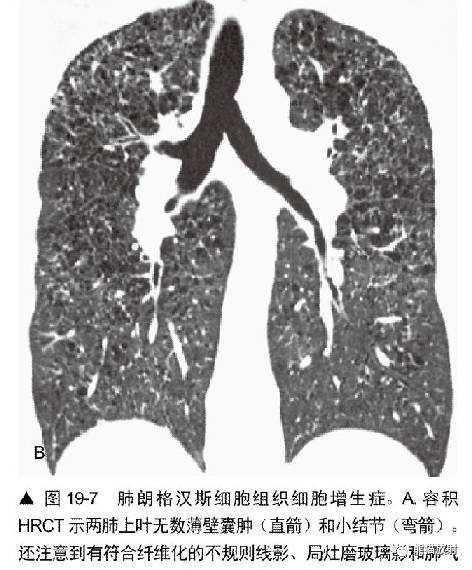

LAM中的肺囊肿与肺朗格汉斯细胞组织细胞增生症(PLCH)中描述的非常相似然而,3种表现常可以区别这两种疾病。

病变主要分布在上、中肺部,基底部相对不累及。